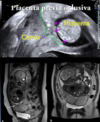

27

¿Cómo se clasifica la placenta previa según su localización?

- Oclusiva: Total o parcial (ocluye el OCI - Orificio Cervical Interno) - No oclusiva: Marginal (adyacente al OCI sin sobrepasarlo) o de inserción baja (<2 cm del OCI)

¿Cómo se diagnostica la placenta acreta?

- Sospecha clínica - Ecografía - Doppler - Resonancia magnética (RNM) 📷